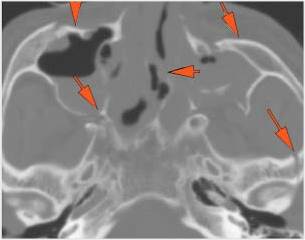

Mandible and Temporomandibular Joints

There is bony injury or displacement of the body, angle, ramus, parasymphyseal region, alveolar ridge, and condylar and coronoid process of the mandible. [In case of fracture, describe complexity and displacement]. [Yes/No]

The condylar head and fossa as well as the temporomandibular joint space are fractured and/or dislocated. [Yes/No]

There is condylar fracture either within or outside of the joint capsule, or with or without involvement of the articular surface of the condylar head. [Yes/No]

There is evidence of radiodense intra-articular osteochondral fragments. [Yes/No]

There is bony injury or displacement of the external auditory canal and/or other evidence of temporal bone injury. [Yes/No]